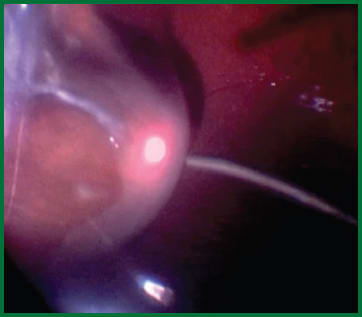

In addition to iatrogenic breaks, intraoperative bleeding is a primary complication in diabetic eyes. One step I often take to reduce the vascularity of the abnormal tissue is to perform an intravitreal injection of bevacizumab within five days prior to vitrectomy (Figure 4).